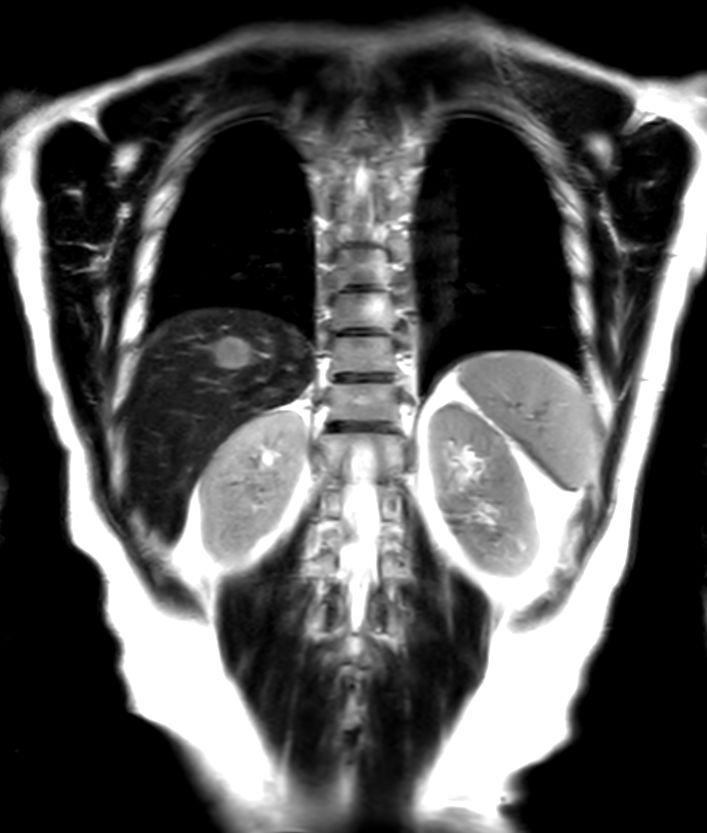

T2w SPAIR - Breath hold

T2w TSE - Breath hold Compressed SENSE